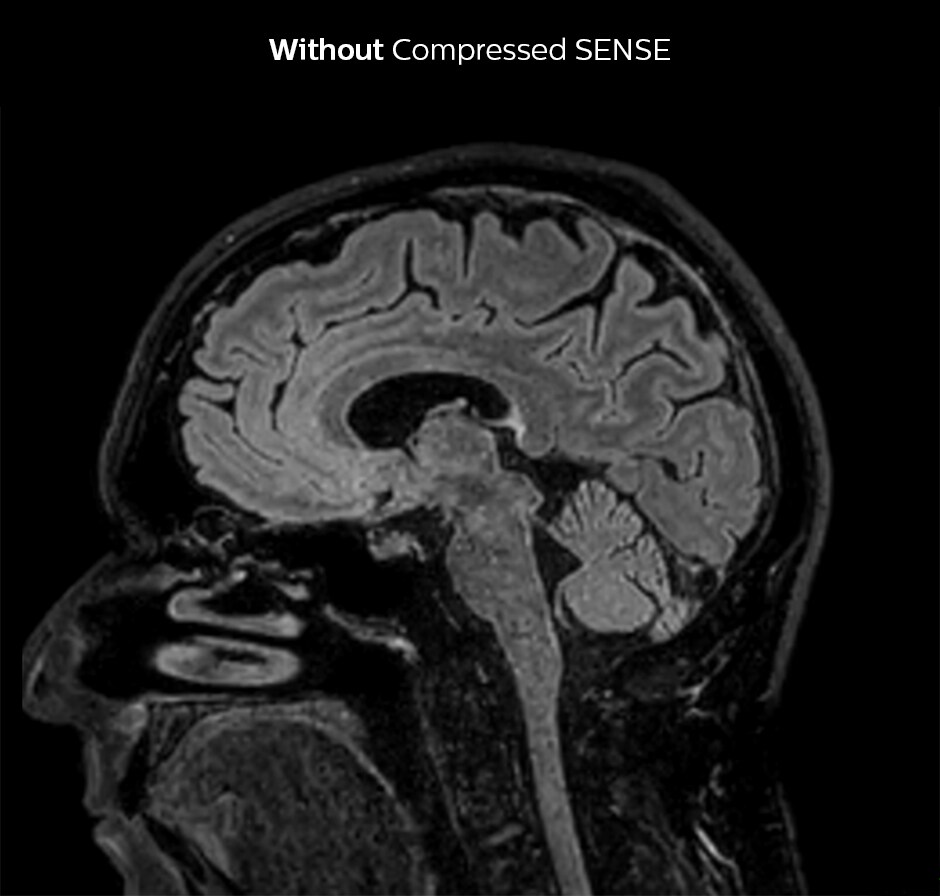

Compressed SENSE allows 28% shorter scan time with the same spatial resolution.

3D FLAIR, scan time 5:02 min, voxel size 1.1 x 1.1 x 1.1 mm, Ingenia 1.5T.

3D FLAIR, scan time 3:36 min, voxel size 1.1 x 1.1 x 1.1 mm, Ingenia 1.5T.